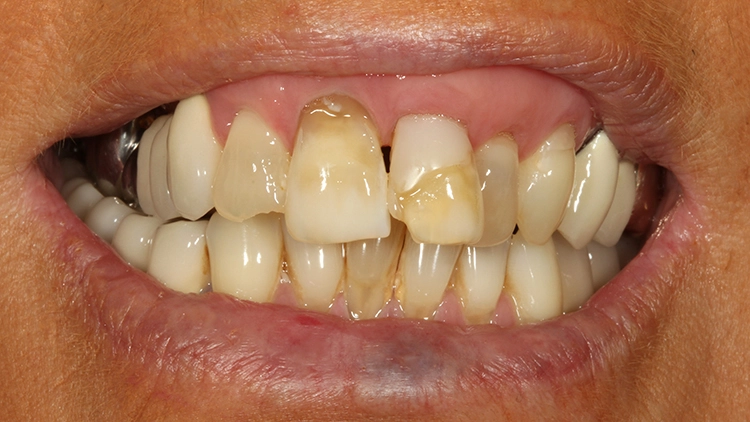

Bei der 61-jährigen Patientin imponierten unterschiedlichste Befunde, die ein ästhetisches Gesamterscheinungsbild gerade der Oberkieferschneidezähne deutlich beeinträchtigten (Ausgangsbefund Bild oben): Labiale und inzisale Zahnhartsubstanzdefekte unterschiedlichster Ausprägung an allen Inzisivi, Verfärbungen der Zähne, eine Fehlstellung sowie multiple Rezessionen und keilförmige Zahnhalsdefekte, die zum Teil von diversen Vorbehandlern mit Zahnhalsfüllungen versorgt worden waren. Es zeigte sich ein Gewebeüberschuss in regio 22, der zumindest teilweise durch die Elongation und Retrusion des Zahnes 22 bedingt zu sein schien. Diese Kombination führte zu einem disharmonischen Gingivaverlauf im Ober- und im Unterkiefer.

Auf die Situation angesprochen, war die Patientin sehr erstaunt zu hören, dass hier doch Behandlungsmöglichkeiten existieren, die das Gesamterscheinungsbild verbessern könnten. Die ansonsten sehr gepflegte und auch auf ihr Äußeres bedachte Dame äußerte dann sehr spontan den Wunsch nach einer Behandlung, als sie über die diversen Therapieoptionen aufgeklärt wurde.

Der Wunsch der Patientin zur ästhetischen Neuversorgung bezog sich primär auf die Oberkieferfront. Dabei kam eine kieferorthopädische Therapie für sie nicht infrage. Fokus in der Beratung lag auf der mukogingivalen Grenzlinie: Vollkeramische Restaurationen können zwar auch bei Befunden wie dem vorliegenden eingesetzt werden, das ästhetische Gesamtbild ist dann jedoch ziemlich eingeschränkt, wenn eine derartige Asymmetrie der Gingivaverläufe der einzelnen Zähne besteht.

Die Patientin wurde eingehend über die Möglichkeiten und das operative Vorgehen der präprothetischen Mukogingivalchirurgie aufgeklärt: Die „Zahnfleischästhetik“ kann durch einen Rückgang, auch aber durch einen Überschuss von Gewebe negativ beeinflusst werden. Korrekturen von diesen Missverhältnissen können demnach durch unterschiedliche chirurgische Maßnahmen vorgenommen werden. Aufgrund von Statur und Gesichtsform der Patientin erschienen die Zähne 13 bis 11 nicht zu lang, weshalb gemeinsam mit der Patientin lediglich eine Korrektur des Gingivaverlaufes im 2. Quadranten eingeplant wurde.